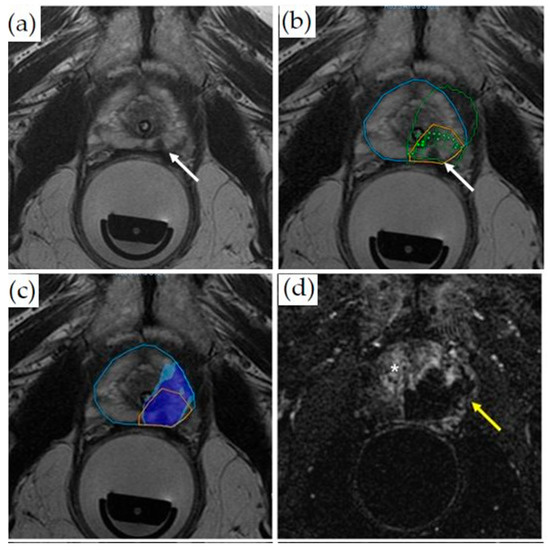

3.1.4. MRI-Guided Focal Laser Ablation